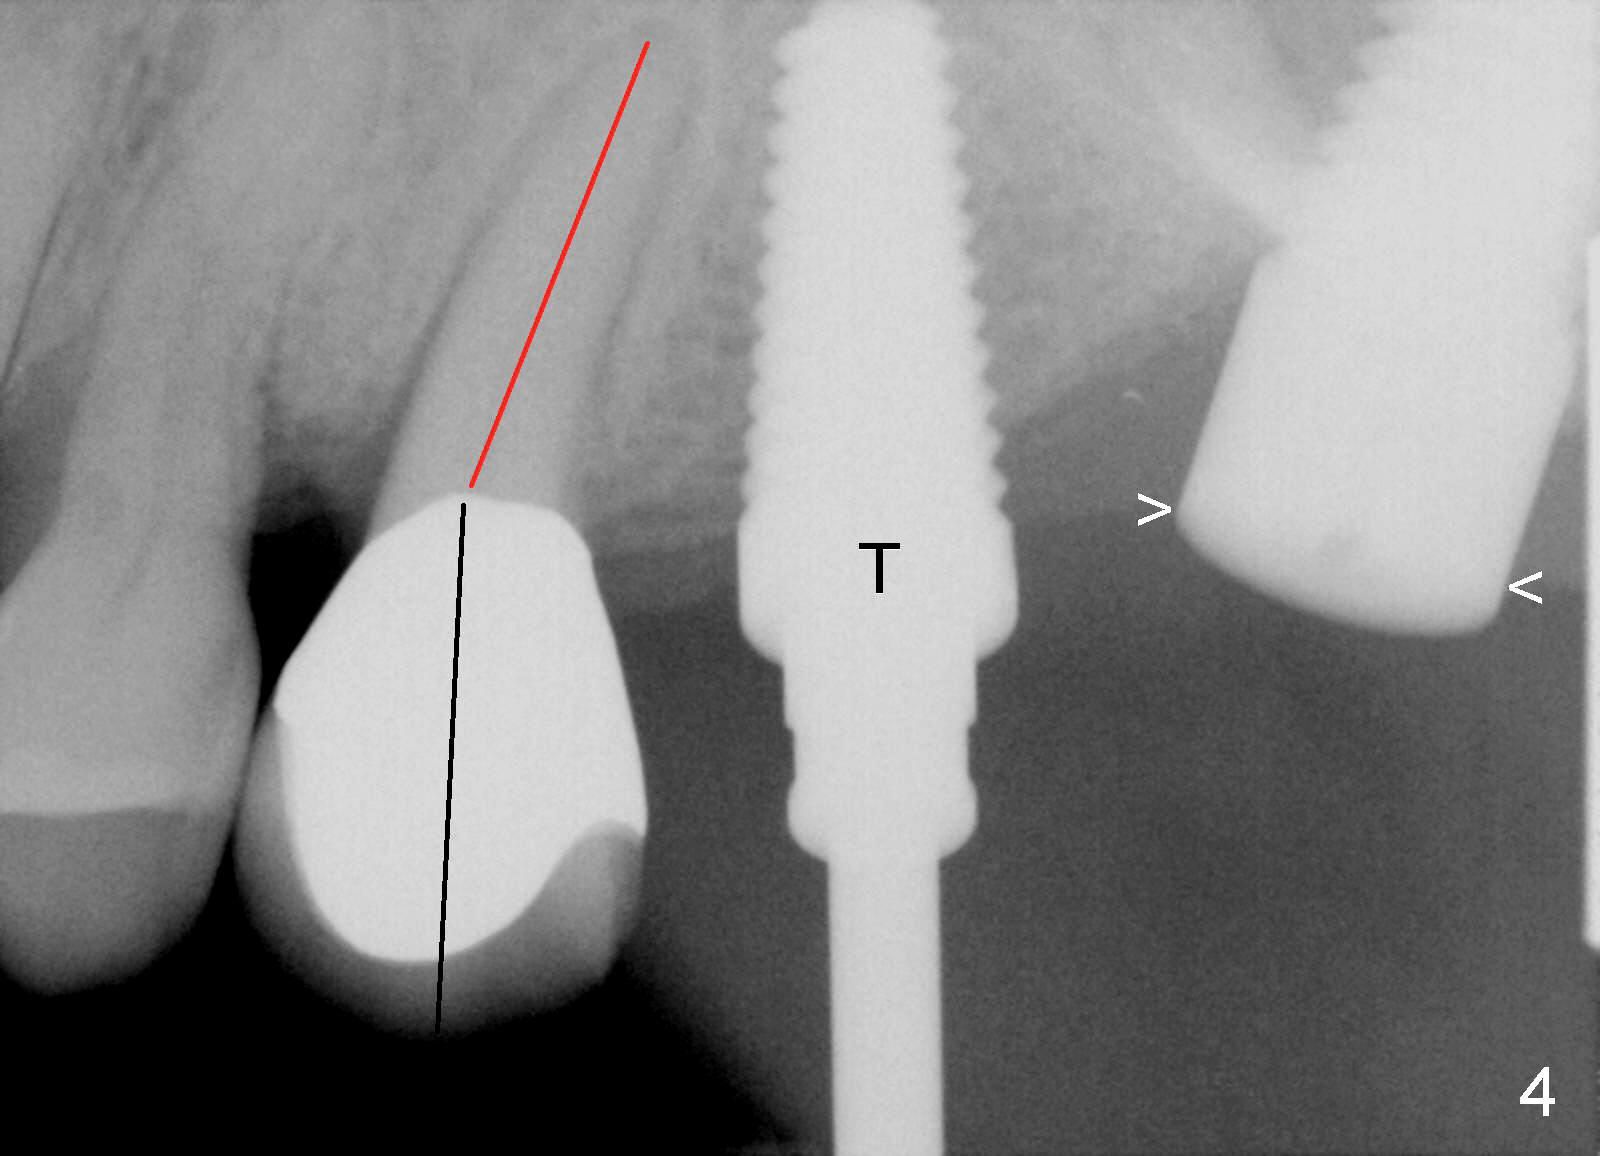

A 58-year-old man used to have a upper left 3-unit bridge. Two months after extraction and immediate implant at the site of the posterior abutment, an implant is planned to be placed at the site of the pontic, #14 (Fig.1). Osteotomy starts with a 1.6 mm pilot drill, followed by bone expanders, parallel to the crown of the tooth #13. The first intraop PA shows that 3.0 mm bone expander is close to the root of the neighboring tooth (Fig.2). No matter what is done to change the trajectory of the osteotomy using expanders according to the crown morphology of the neighboring tooth, the next 3 expander does not improve in parallelism (Fig.3). When a 6x17 mm tap is inserted (Fig.4 T), it is realized that axis of the tap is parallel to the axis of the crown of the neighboring tooth (black line), but not that of the root (red line). It is too late to change the trajectory drastically; a 6x17 mm implant is placed with insertion torque > 60 Ncm (Fig.5). It is best to change the trajectory as early as possible, e.g., after taking the first intraop PA and withdrawing the expander (Fig.6 black area) and as much as possible (red line; starting new osteotomy). It is quite similar to immediate implant. There is no bone loss 2 months postop (Fig.7), 18 months (Fig.8,9) or 34 months (Fig.10)post cementation, in spite of open contact between the crowns (Fig.10 black arrowhead). This is partially due to supragingival margin (Fig.11,12 (immediately pre-cementation)). No bone loss is noted 3 years 5 months post cementation (Fig.13).